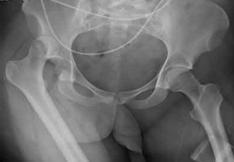

10. LUXACIÓN DE CADERA

La luxación de cadera ocurre con frecuencia en los jóvenes debido a accidentes de tránsito. En forma general se dividen en luxaciones anteriores (anteroinferior o anterosuperior) y posteriores (posteroinferior o posterosuperior).

Luxación de cadera posterior

Es la más frecuente de las luxaciones de cadera y el mecanismo de lesión principal es por accidentes en tránsito.

Clínica: Dolor, impotencia funcional y deformación. La posición que adopta el miembro afectado incluye rotación interna, semi flexión, aducción y acortamiento ENAM 2013-B / ENAM 2012-A).

Tratamiento: La reducción debe incluir como concepto general tracción y rotación externa. Puede realizarse en decúbito prono o supino, sin embargo, en ambos casos deben participar dos personas y el paciente debe estar sedado con relajación muscular.

Complicaciones: Lesión neurovascular, que incluye lesión del nervio ciático, puede estar asociado a fractura de acetábulo, siendo ésta la fractura asociada más frecuente. Asimismo, puede haber fracturas de la cabeza del fémur.

Luxación de cadera anterior

El principal mecanismo de lesión es la abducción forzada (Ej., accidentes de tránsito en motocicleta, deportistas).

Clínica: Rotación externa, abducción y flexión

Complicación: compromiso del VAN femoral, asimismo, puede estar asociado también a fractura de acetábulo .

La luxación traumática más frecuente es la luxación posterior

Figura 74. Posición característica de la luxación anterior de cadera